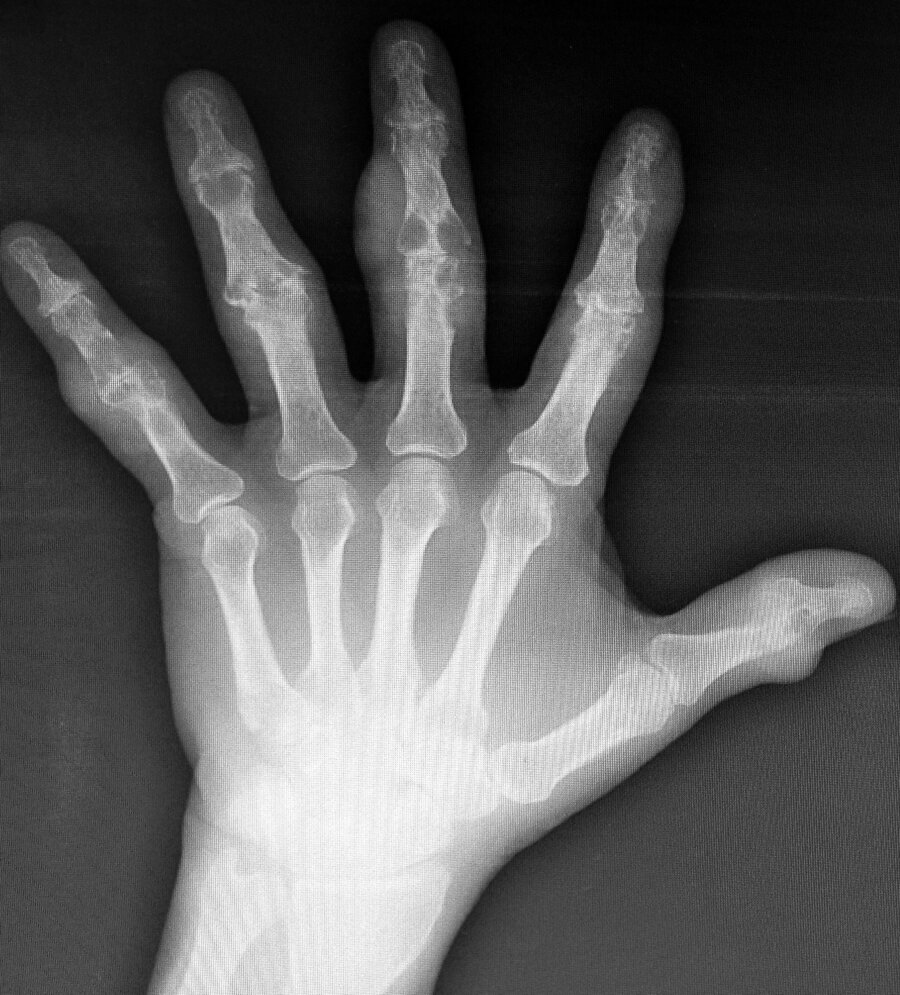

A 52-year-old man is evaluated for chronic pain in the joints of the hands, ankles, and toes.

A radiograph of the hand is shown.

Which of the following is the most likely diagnosis?

A) basic calcium phosphate deposition

B) calcium phosphate deposition disease

C) Gout

D) osteoarthritis

Gout